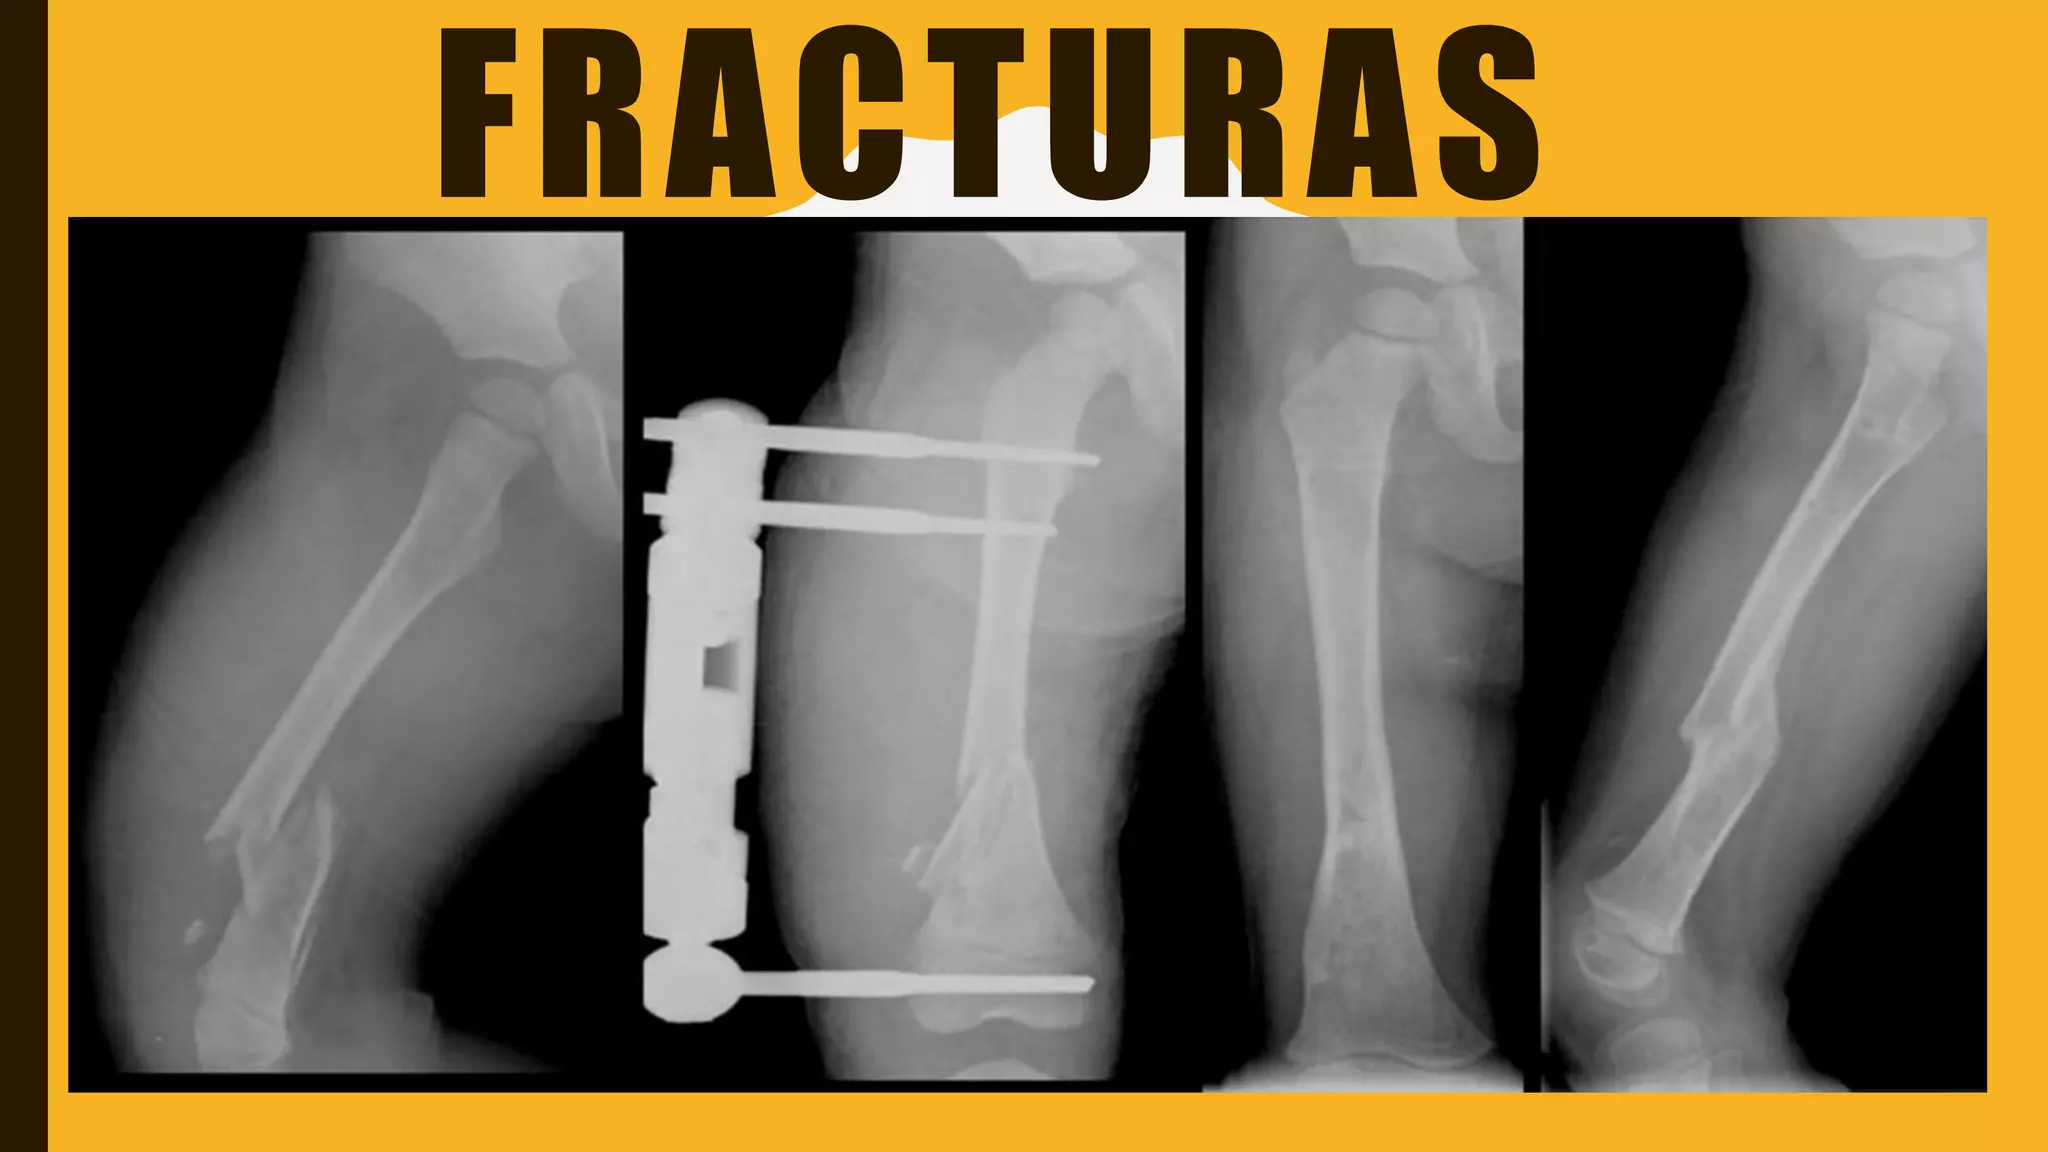

EXPLORACIÓN RADIOLOGICA

Es imprescindible para la evaluación de la fractura. No solo no

confirma el diagnostico, sino que establece las características de

la fractura.

En caso de dudas puede ser necesario el uso de otras

proyecciones, radiografías en estrés o recurrir a técnicas de

imagen como TAC, ganmagrafías o tomografías.